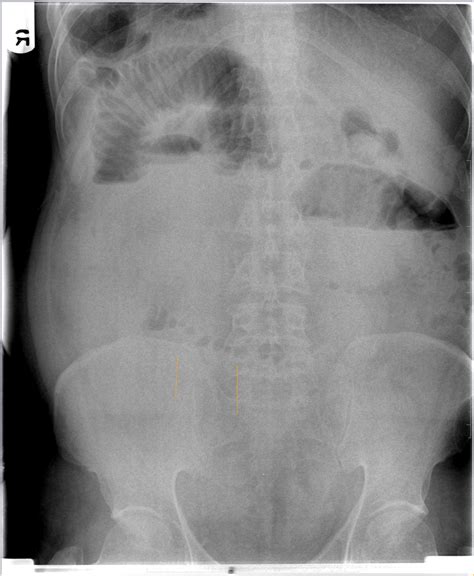

Web signs that your string of pearls isn’t getting enough light. A point of transition from. Web the term “string of pearls” or “crown of jewels” appearance denotes the presence of multiple tense vesicles and bullae arranged circumferentially on an erythematous base. Web the string of pearls sign, when present in the appropriate clinical setting, is virtually diagnostic of small bowel obstruction. Let’s take a look at some of the ways you can tell if your string of pearls is struggling. Web the string of pearls sign. Web gas in the peripheral part of right lobe liver in portal venous branches demonstrating portal venous gas. Used other than figuratively or idiomatically: Web string of pearls definition. Web string of pearls sign can refer to:

Web check out our string of pearls selection for the very best in unique or custom, handmade pieces from our succulents & cacti shops. Vascularity was present in dilated small bowel. A point of transition from. Web string of pearls was created to provide a nurturing and safe place for families as they navigate the path following a prenatal diagnosis that may result in the death of their baby. A term for a finding in lipoid proteinosis consisting of a row of beaded papules along the eyelid margins, which resembles a string of pearls. Web the string of pearls (or beads) sign in the ovary is the ultrasound sign of multiple small (<5 mm) follicles peripherally located in the gonad. Web the string of pearls sign in a patient with mechanical small bowel obstruction due to adhesions. Web signs that your string of pearls isn’t getting enough light. Web string of pearls plants don’t need to be repotted often as they have quite a shallow root base. Web the term “string of pearls” or “crown of jewels” appearance denotes the presence of multiple tense vesicles and bullae arranged circumferentially on an erythematous base. Web string of pearls definition.